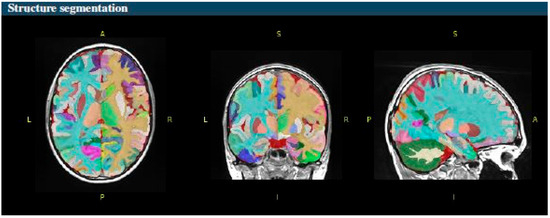

- Subcortical structure segmentation: volBrain’s subcortical structure segmentation is particularly noteworthy, as it delivers highly accurate and reproducible results for critical structures such as the hippocampus, thalamus, and caudate nucleus. The platform’s unique approach, which includes modifications to the non-local label fusion algorithm, further enhances the quality and consistency of the segmentation results.